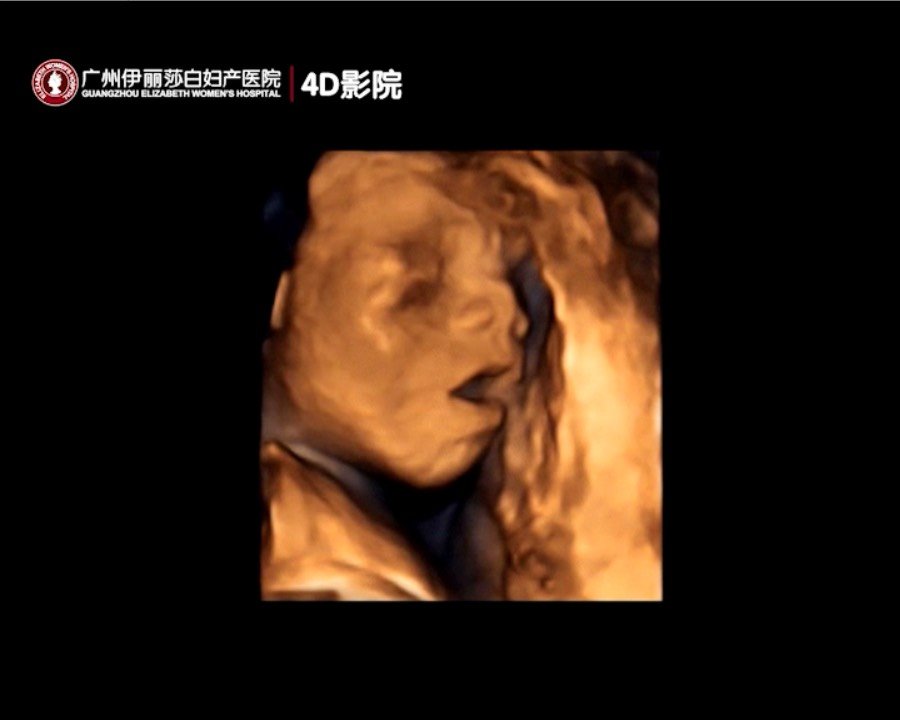

24周的小宝打哈欠,玩脚趾头,好可爱呀 24周的小宝打哈欠,玩脚趾头,好可爱呀 点击展开 丹妮宝贝0813 2016-05-11 22:58 为您推荐: 其他回答 我那时是刚好过了时间做不了 @菡萏 2016-05-11 23:13 恭喜^_^ Lu·lu 2016-05-11 23:06 呵呵幸福吧 Gjglxdc 2016-05-11 23:03 。。。。。。。 糜酒长安 2016-05-11 23:03 恭喜恭喜, 小艾媽媽 2016-05-11 23:02 加载更多 相关问题 小宝老是打哈欠这可咋整啊 小宝老是打哈欠可是都不睡是什么问题 13周,老是打哈欠好吗